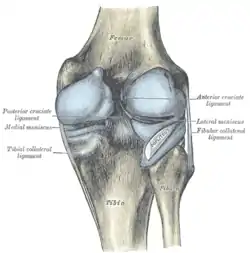

Head of right tibia seen from above, showing menisci and attachments of ligaments. Capsule of right knee-joint (distended). Posterior aspect.

Magnetic resonance imaging evaluation demonstrating normal signal of both anterior and posterior cruciate ligaments (arrows). Anterior view of knee.